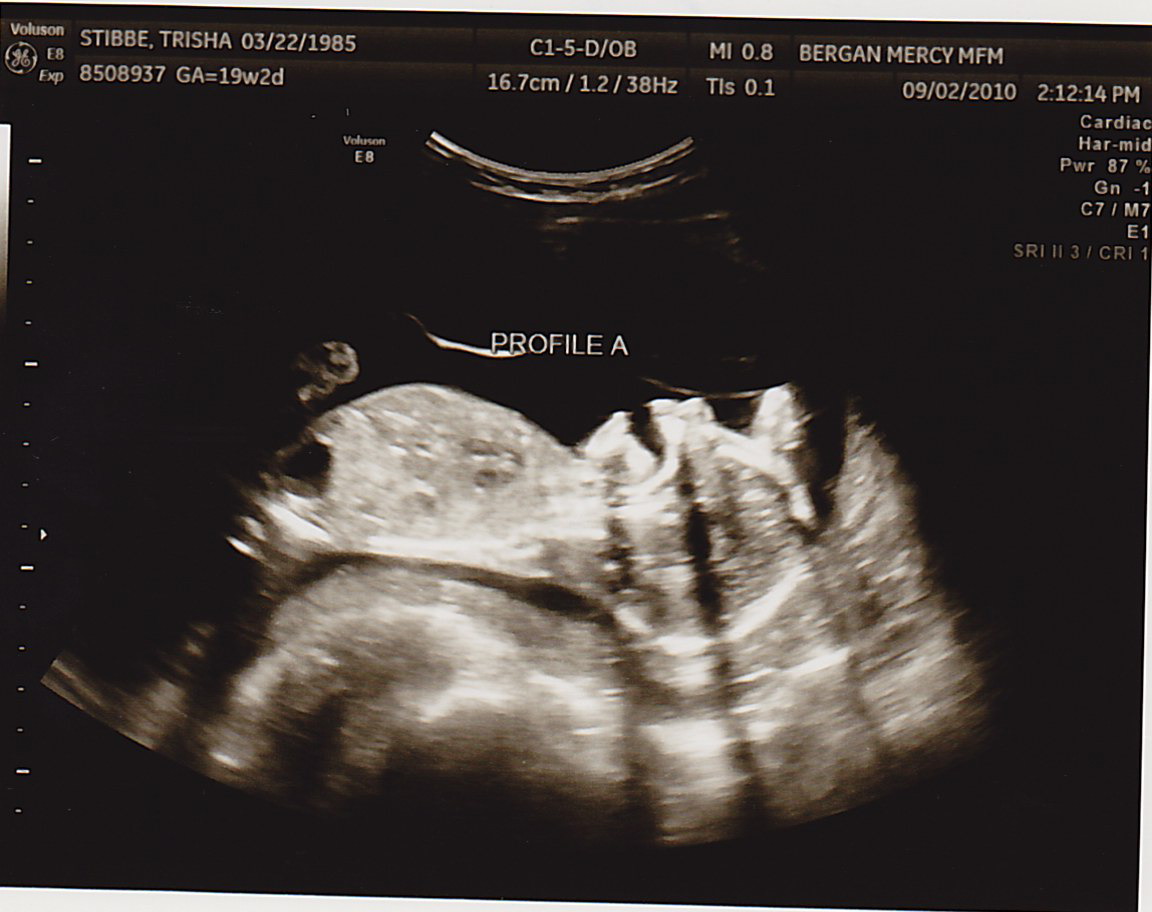

TODAY was a great appointment- we found out Baby B had a lot more fluid around himself!!! That means I didn’t have to have more fluid drained (at least for today). Baby A was 8oz and Baby B was 6oz. This is still good news, because two weeks ago Baby A was 6oz and Baby B was 4oz. As long as they’re both gaining the same amount of weight from here on out, we’re very positive everything will be okay. The difference between them just needs to continue to lessen.